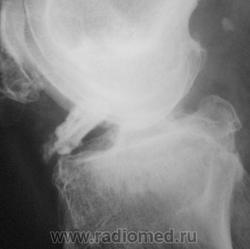

Как бы артроз, то артрозом, а дополнительное образование - костный фрагмент ?, инородное тело?, остеофит !? Он вообще сгибается?

Интереснейшая и редкая картинка! Первое впечатление, что это инородное тело в таком футляре из соединительной ткани. Валентин Львович, расскажите, будьте любезны, что же тут такое????

Инородного тела нет, не было травмы в ближайшее время. В настоящее время пациент находится в ОКБ, лежит в травматологии.

Да такой "футляр" ... десятилетия копится. Явно не в последние годы повреждение. Не вижу места, откуда бы оторвался фрагмент, и на остеофит явно не тянет. Очень любопытно, что на артроскопии... Если узнаете дальнейшие перипетии пациента, то отпишитесь, пожалуйста!

Пациенту в области делали толи КТ, толи МРТ сустава, точно не знаю, но он (пациент) еще не возвратился.